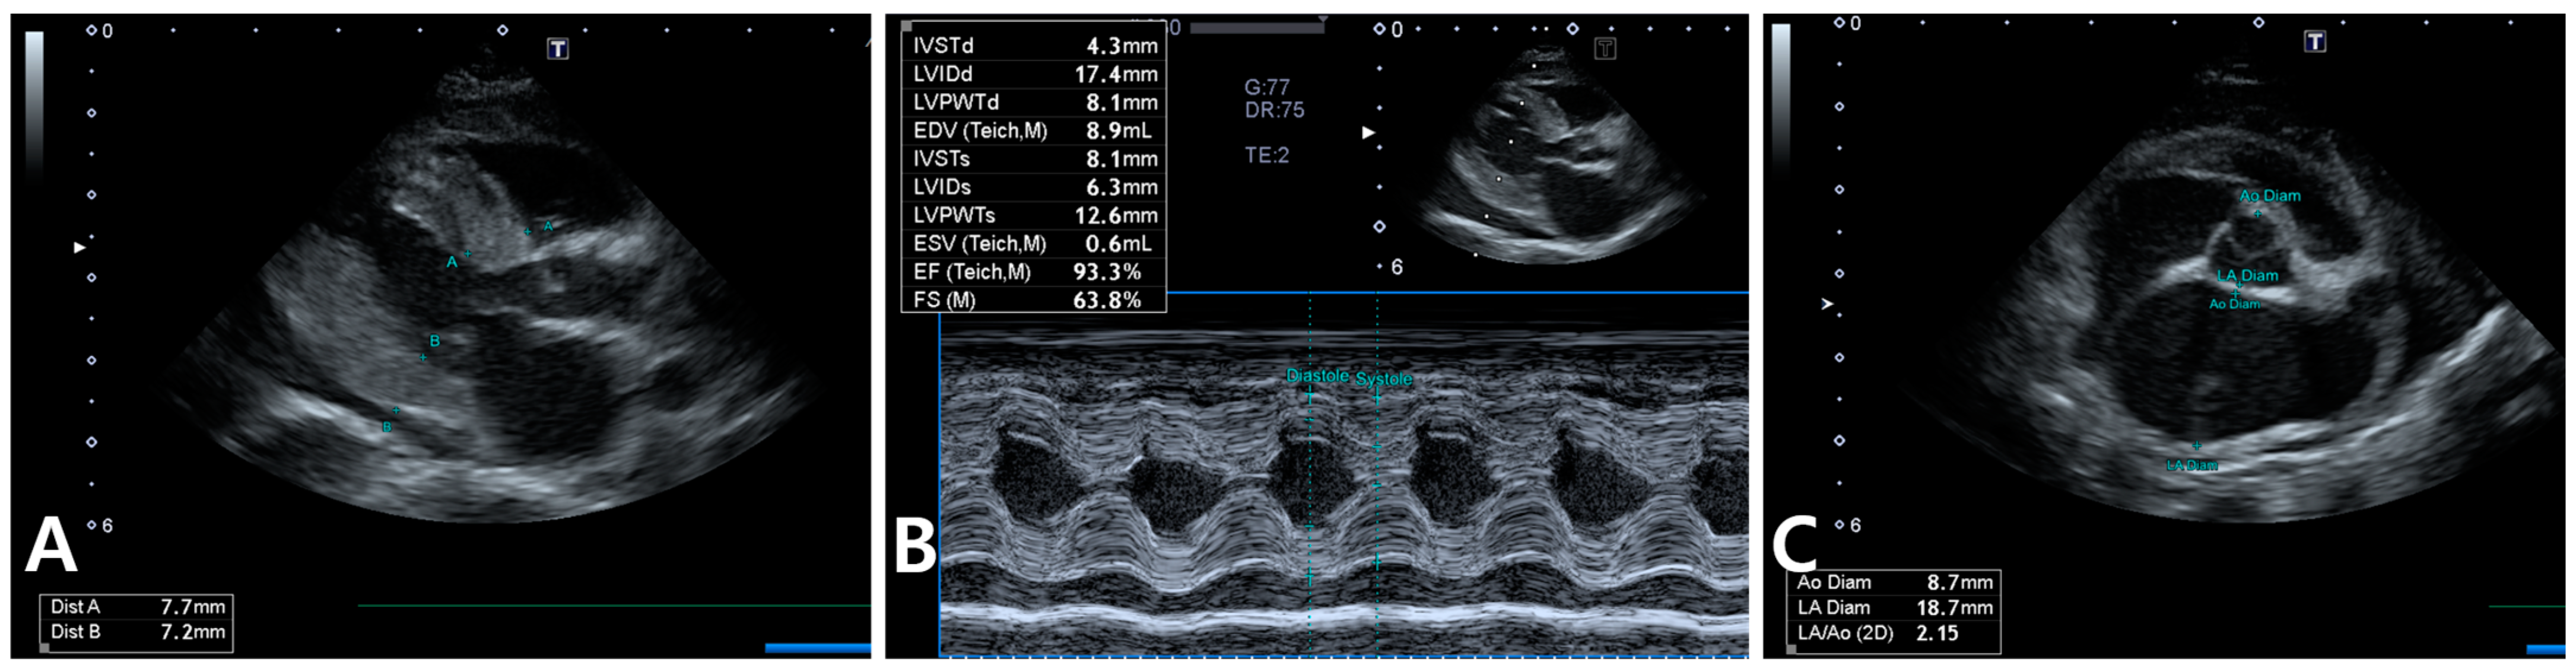

2. Case Description